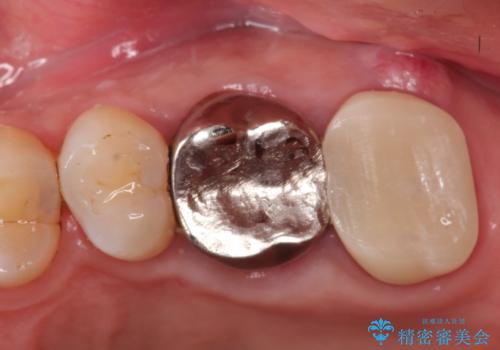

【歯牙破折】インプラントによる咬合回復

- 痛みを主訴に来院されました。

歯牙の破折を認めたため抜歯をし、インプラントにて咬合回復をしました。

抜歯後、骨増生を行ったのちインプラントを埋入しています。